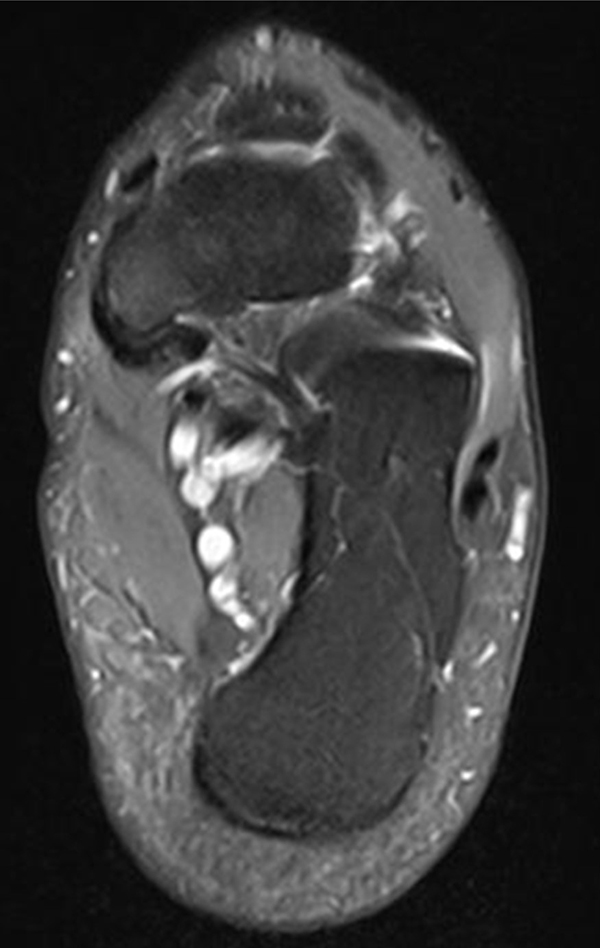

Abbildung 2.1.

Bildbeispiele symptomatische OCL

Zum Lesen der Bildbeschreibung und zur Vollansicht bitte das Bild anklicken. Bild: H. C. Rischke